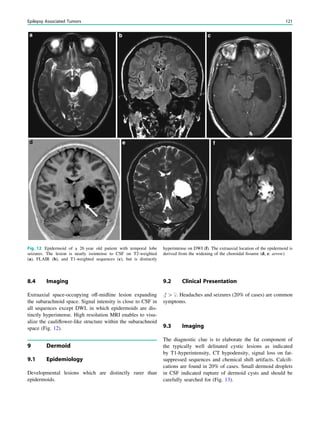

Kleffner syndrome, but the results are variable (Cross and

Neville 2009).

5.2 Surgical Technique

The cortical area for MST is defined anatomically (neuro-

navigation is essential) and/or electrophysiologically with

intraoperative eletrocorticography. The subpial transsec-

tions are performed with specially designed knives (Morrell

et al. 1989). After a small pial opening, intragriseal inci-

sions spaced at 5-mm intervals are placed over the crown of